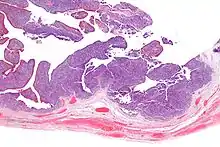

Micrograph of transitional cell carcinoma of the ovary. H&E stain. |

Transitional cell carcinoma of the ovary (TCC of the ovary) is a rare type of ovarian cancer that has an appearance similar to urothelial carcinoma (also known as transitional cell carcinoma).[1]

TCC of the ovary is diagnosed by examination of the tissue by a pathologist. It has a characteristic appearance under the microscope and distinctive pattern of immunostaining.[2]